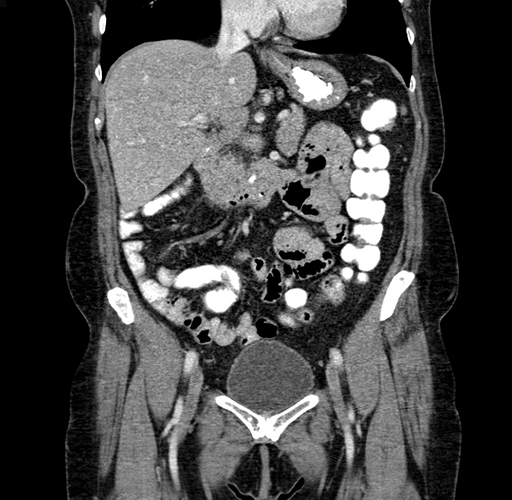

Pre-Chemo: Coronal Venous

Coronal Venous